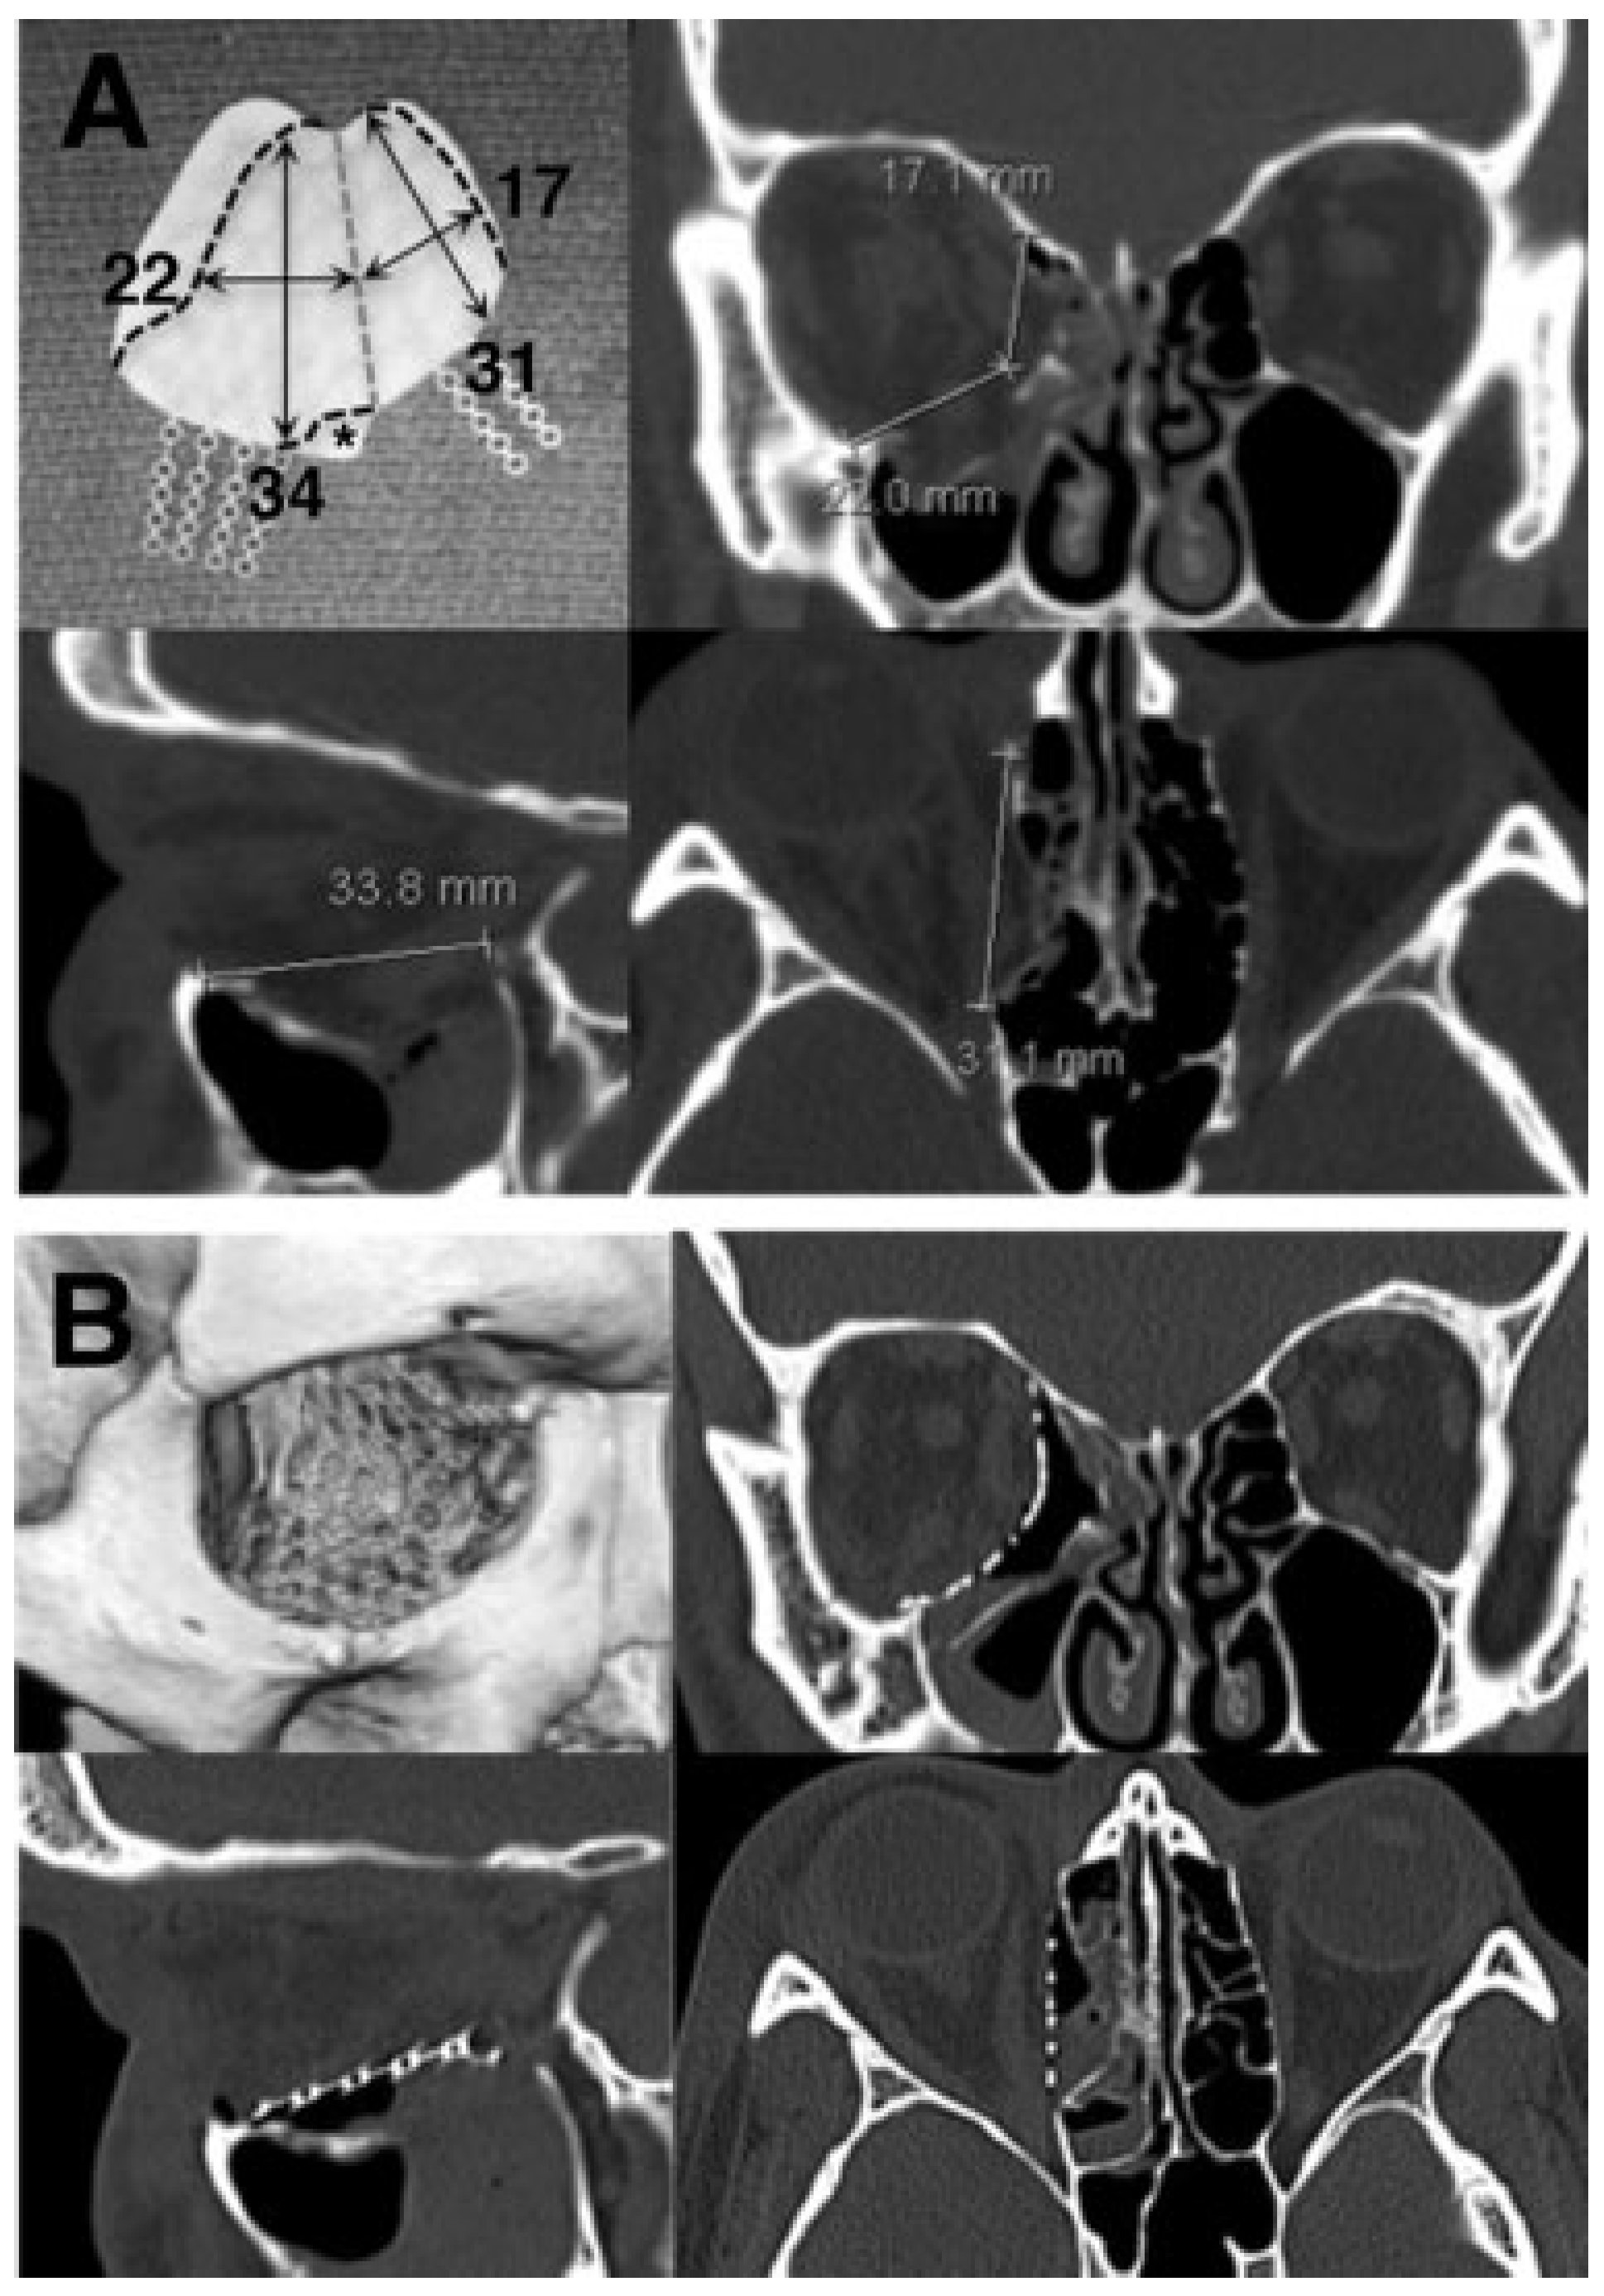

Preoperative planning included detailed measurements tak-en from the orbital CT scan using the caliper function on the hospital’s imaging system to determine the size and shape of the implant (Figure 2). Coronal measurements were used todetermine the width of the floor and medial wall compo-nents; the axial and sagittal measurements dictated the anterior-to-posterior length of the medial wall and floor, respectively. The flex point between the floor and medial portions of the implant approximated the position of inferomedial strut on the uninjured side. All implant meas-urements took into account the need for a sufficient amount of overlap over the bony ledges. Serial measurements were taken at set image intervals for each case, typically every 4 to 5 mm.

The implant material used in all cases was a preshaped PPE-imbedded titanium mesh implant specifically designed for orbital floor and medial wall reconstruction (Medpor Titan OFW, Stryker, Kalamazoo, MI). The implant was soaked in antibiotic solution and trimmed to the predetermined dimensions. It was then bent to conform to the natural bony contours of the orbit (Figure 3), reproducing the upward posteromedial slope of the floor, the anterior-to-posterior S-shaped curvature, and the ~ 120-to 130-degree angle between the floor and medial wall. With the orbital contents retracted and bony ledges exposed by ribbon retractors, the implant was placed within the subperiosteal space to cover the defect. Care was taken to ensure that the edges of the implant rested securely on stable bony ledges, and that no orbital soft tissue was incarcerated beneath the implant. Forced duction testing was repeated to confirm normal globe mobility. The anterior titanium extensions of the implant were then secured to the inferolateral rim and frontal process of the maxilla with titanium screws. In most cases, only two of the extensions were fixated (laterally and superomedially), and the remainder were broken off and discarded. The lateral canthal tendon was resuspended from the periosteum behind the lateral orbital rim with a 4–0 polydioxanone suture, and the conjunctiva was closed with buried interrupted 6–0 plain gut sutures.

The second approach—single-implant repair—has been described by several authors. Nunery at al reported the use of a “wraparound” nylon foil implant to repair these defects [8] . Although their results were excellent overall, only 14 of 102 cases involved the inferomedial strut. The use of such a flexible material to span these large defects raises the theo-retical concern of implant buckling and displacement. Addi-tionally, nylon foil’s lack of malleability is problematic when attempting to replicate the normal contours of the floor and medial wall. Other reported single-implant techniques utilize titanium mesh plates, which are either individually pre-formed based on preoperative stereolithography or manufac-tured to replicate the bony contours of the floor and medial wall (Matrix Midface preformed orbital plate, Synthes Inc., West Chester, PA) [9,10] . Although in theory, these implants, if placed properly, should produce excellent anatomic results, we avoid their use for two reasons. First, the size of the premanufactured implant is not large enough to completely cover many of the defects we encounter. The second reason is our own experience as well as that of other authors with orbital adherence syndrome caused by exposed titanium mesh in the orbit.14 The use of PPE-imbedded titanium for the repair of floor and medial wall fractures has been described by several authors [15,16,17,18,19] . but this to our knowledge is the first published report utilizing the preshaped orbital floor/wall implant designed by Holck (Medpor Titan OFW, Stryker, Kalamazoo, MI). This implant combines the capacity of PPE for fibrovas-cular ingrowth with the strength and malleability of titanium mesh, along with the additional benefits of a preshaped design and titanium extensions for screw fixation to the orbital rim. The size and shape of the implant is intended to provide coverage for the largest possible fractures, and requires trimming to fit most orbits (Figure 2). It is currently available in three versions: porous on both sides (MTM), nonporous (barrier) on both sides, or a combination (MTB)

Proper implant sizing and shaping is critical to the success of this technique. Given the relatively large surface area of the implant, the rigidity of the material, and the close proximity of the implant to vital orbital structures, seemingly small deviations in contour and shape can potentially result in significant complications. Therefore, we highly recommend the use of preoperative CT scan measurements to determine the appropriate dimensions of the implant (Figure 2). When shaping the implant prior to insertion, careful attention must be paid to replicating the slopes and curves of the floor and medial wall [29] . and a thorough three-dimensional under-standing of the complex anatomy of the bony orbit is an absolute prerequisite to using this technique (Figure 3).

Figure 2. (A) Preoperative computed tomography measurements were taken in all three imaging planes at multiple levels to determine the implant dimensions (single cuts shown here). Note that the axial measurement of the medial wall begins behind the posterior lacrimal crest. Top left, the orbital floor/wall implant with black dashed lines showing areas to be trimmed, and a gray dashed line showing the planned flexure point between the floor and medial wall. Area marked with asterisk (*) is trimmed to make room for the nasolacrimal duct and inferior oblique origin. (B) Postoperative computed tomography scan images and three-dimensional reconstruction showing implant placement in the same patient.